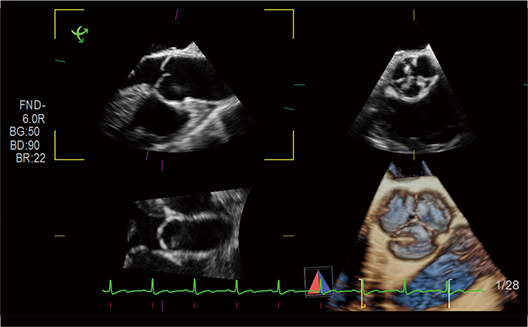

Automatic calculation of Ejection Fraction from 3D volume data. The BiPlane images (4ch and 2ch) are displayed with ED/ES frames selected automatically.